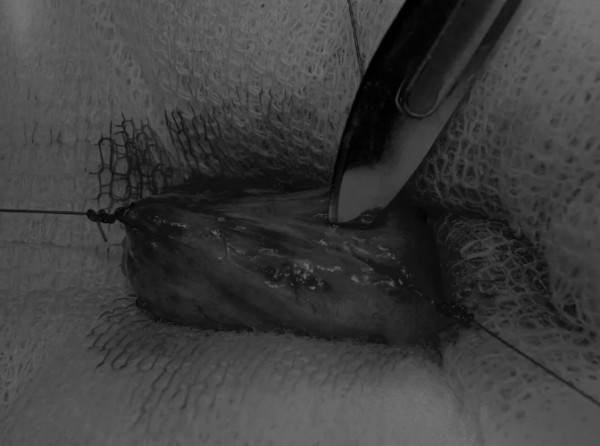

在牵引缝线之间选择血管扩张较差的区域用手术刀切开膀胱壁(图3)。在牵引缝合线之间用手术刀在血管不良的区域做切口。切开膀胱壁后,膀胱内的手术可按手术方案实施,例如取出结石(图4)。

文章详情图片

图3 避开主要的膀胱血管,做一个尽可能小的切口